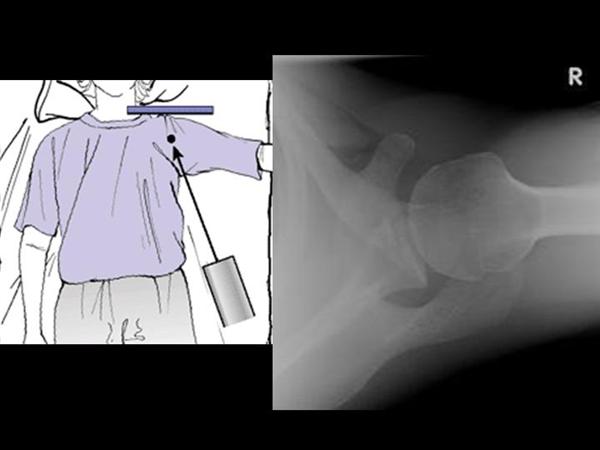

3. axillary lateral view

팔이 안벌어지는 경우에는 velpeau view 를 촬영해 볼 수 있습니다.

상완골의 탈구/아탈구 를 확인해 볼 수 있습니다.